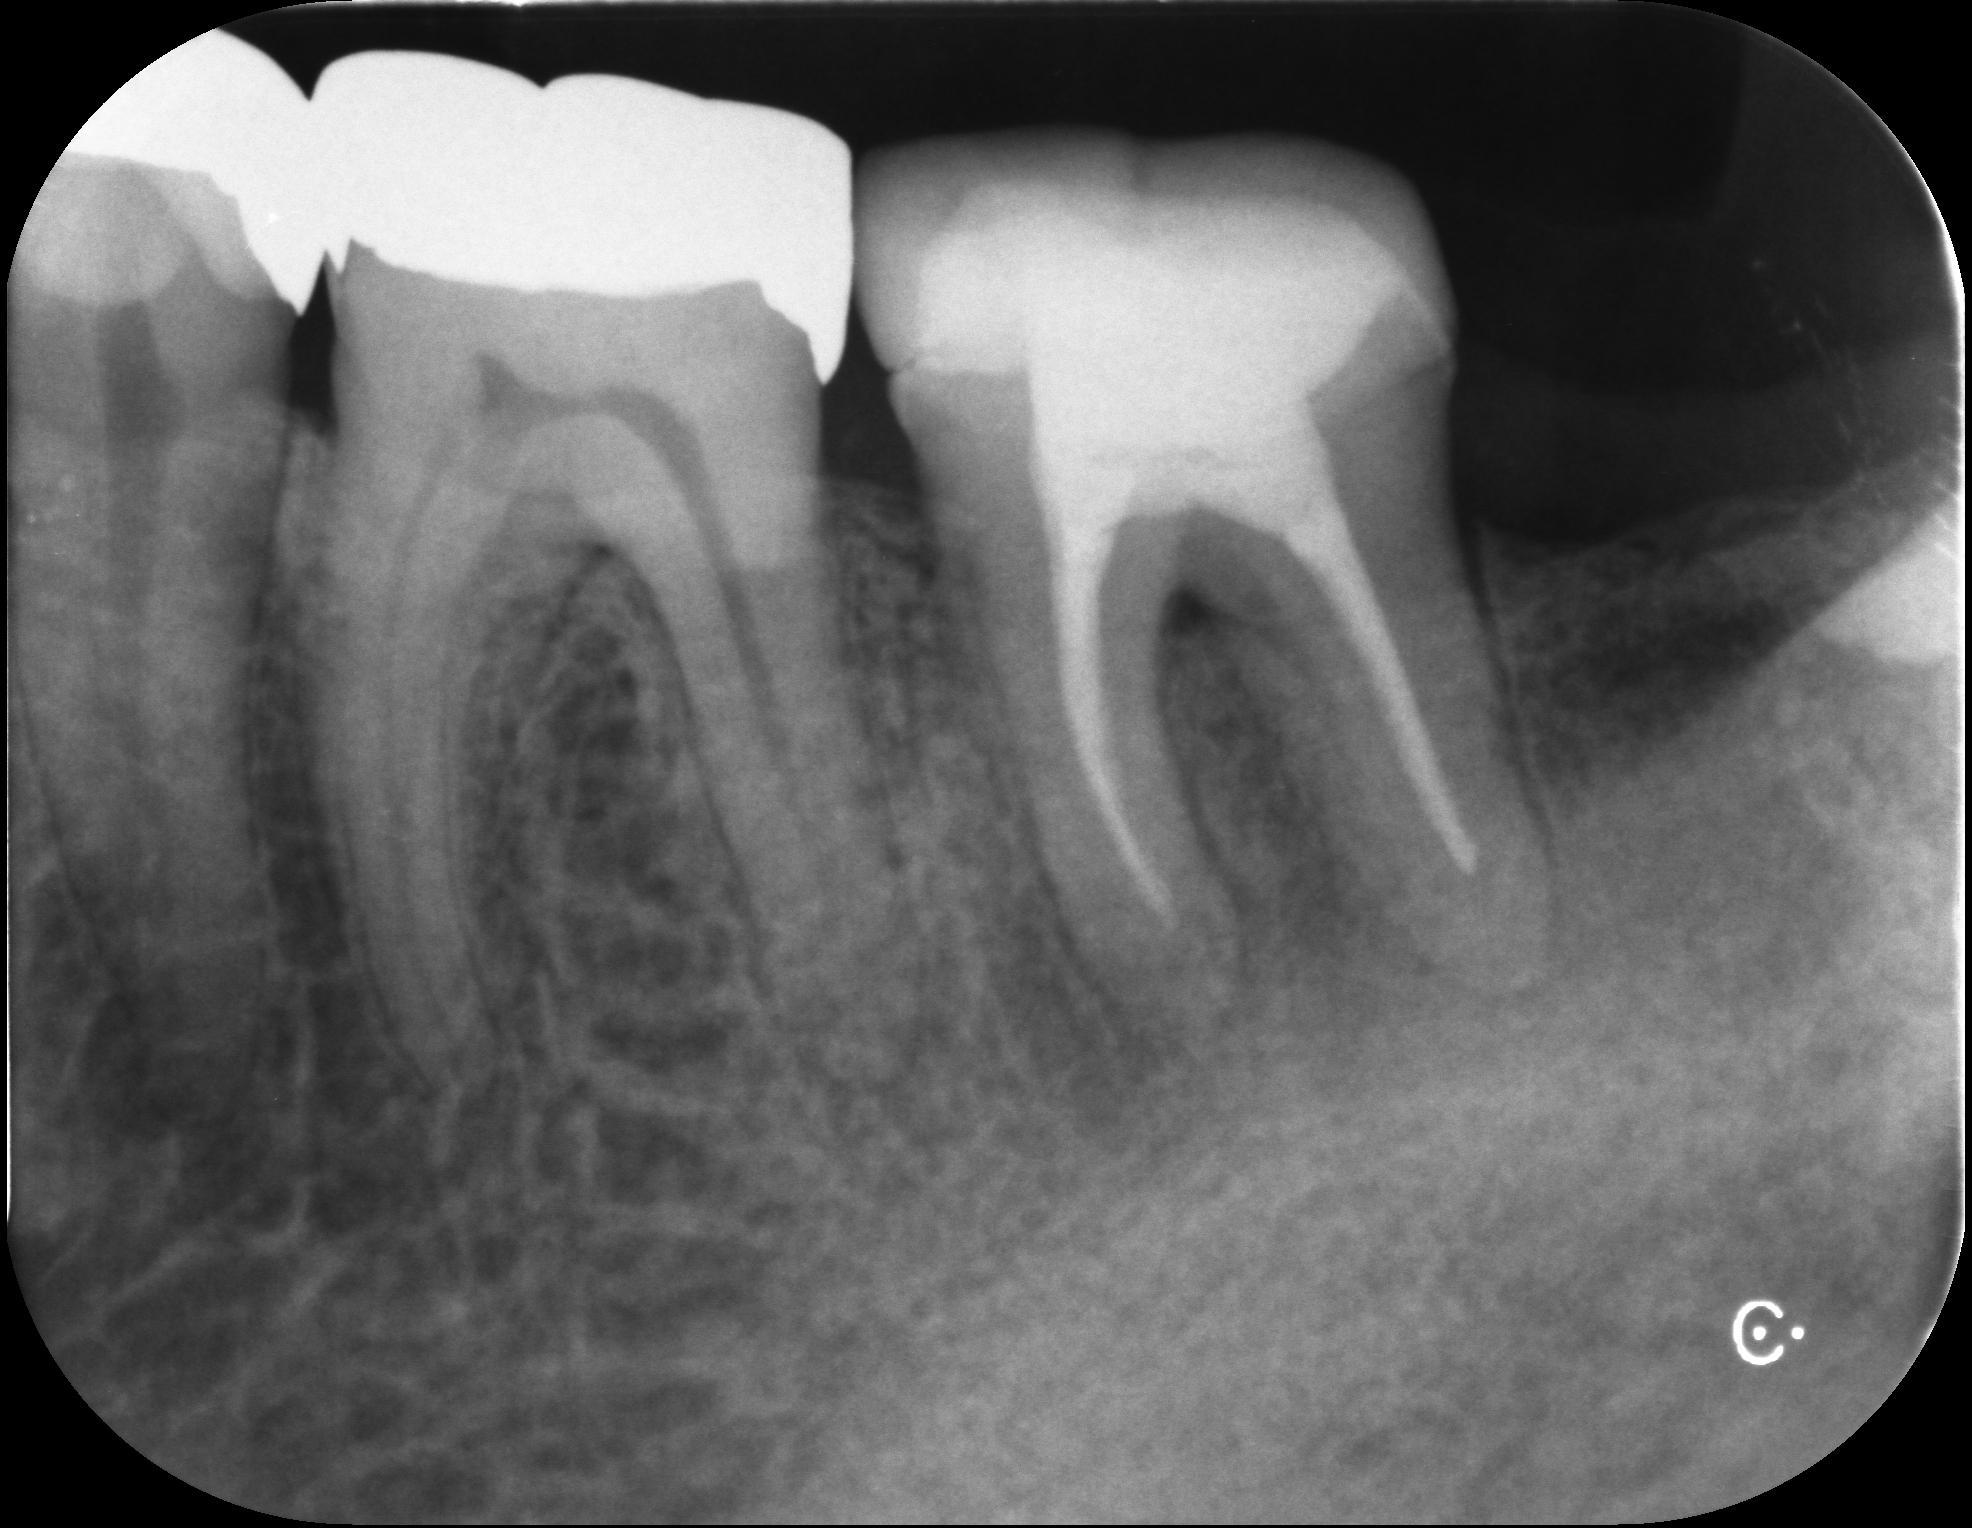

自家歯牙移植(じかしがいしょく)は、虫歯や歯周病で歯を失った部分に、自分の親知らずなどを移植する治療法です。歯根膜(しこんまく)という組織を活かせるため、自然な噛み心地が得られ、5年生存率も高い特徴のある治療法です。

患者様の移植に使用する歯が智歯(ちし=親知らず)であれば保険適応となっており、移植後に根管治療は必要なものの、生着するとご自身の歯をそのままお使い頂けるため、とてもメリットのある治療です。